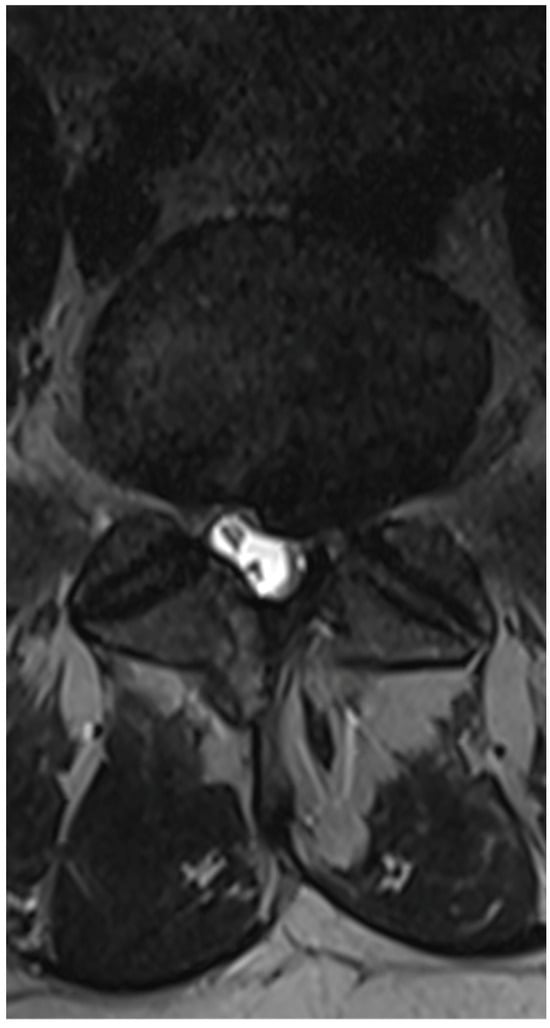

3.6. Case 3: Transient Paraparesis following Iatrogenic Vascular Fistula of the Dural Sac

- Case 3: Our review did not uncover any literature on intradural hematomas following endoscopic surgery. While there are isolated reports of such hematomas in other contexts [50,51], the dramatic progression and conservative management decision in our case are unique and underscore the need for cautious postoperative monitoring and possibly early intervention in similar future cases.